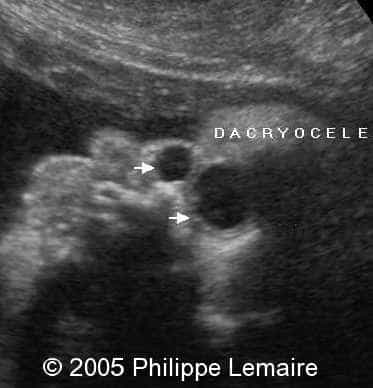

Dacryocystocele, 3D rendering

This is  a 3D-scan of bilateral dacryocystocele.